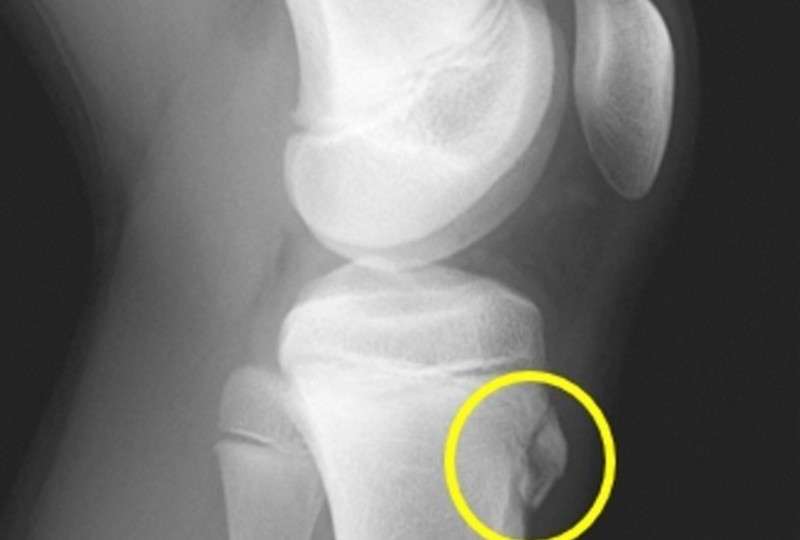

・画像での診断(レントゲン写真)

黄色い丸で囲った部分に太ももの前面の筋肉(大腿四頭筋)が付着します。

上記のレントゲン写真では、脛骨粗面が大腿四頭筋に引っ張られるストレスがかかり、骨の形が不整になっており、突出しています。

上記画像所見と、脛骨粗面を押した時の痛みともも前の筋肉(大腿四頭筋)をストレッチした時に膝関節前面の痛みが出現したことから、オスグット・シュラッター病と診断し、リハビリテーションを開始しました。